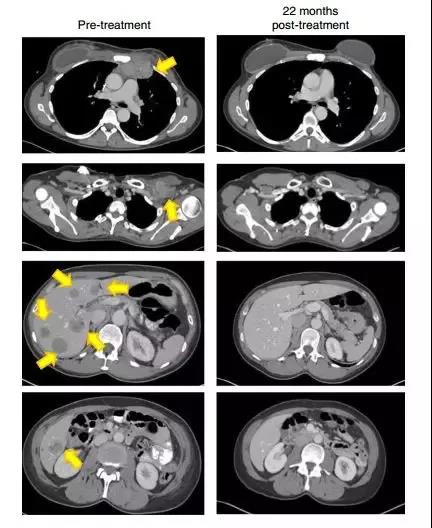

一名患有转移性鳞状细胞癌并接受了多种联合化疗方案,包括顺铂,长春新碱和博来霉素,然后用吉西他滨加顺铂联合放疗。随后发现转移,包括主动脉旁,双侧肺门,颅下和髂骨部位(图1A和1C)。治疗后,她在所有疾病部位都完全消退(图1A和1C)。

另一患者患有转移性腺癌。她的原发性肿瘤对化放疗无效。随后转移到更多的腹膜后淋巴结和肝脏表面,在TIL治疗前,她在腹膜后,腹壁,旁系,肝旁和盆腔部位有肿瘤进展(图1B和1d)。在治疗后,出现完全的临床缓解(图1B和1d)。

22个月后,这名患者的肿瘤(黄色箭头)消失得无影无踪(图片来源:《Nature Medicine》)